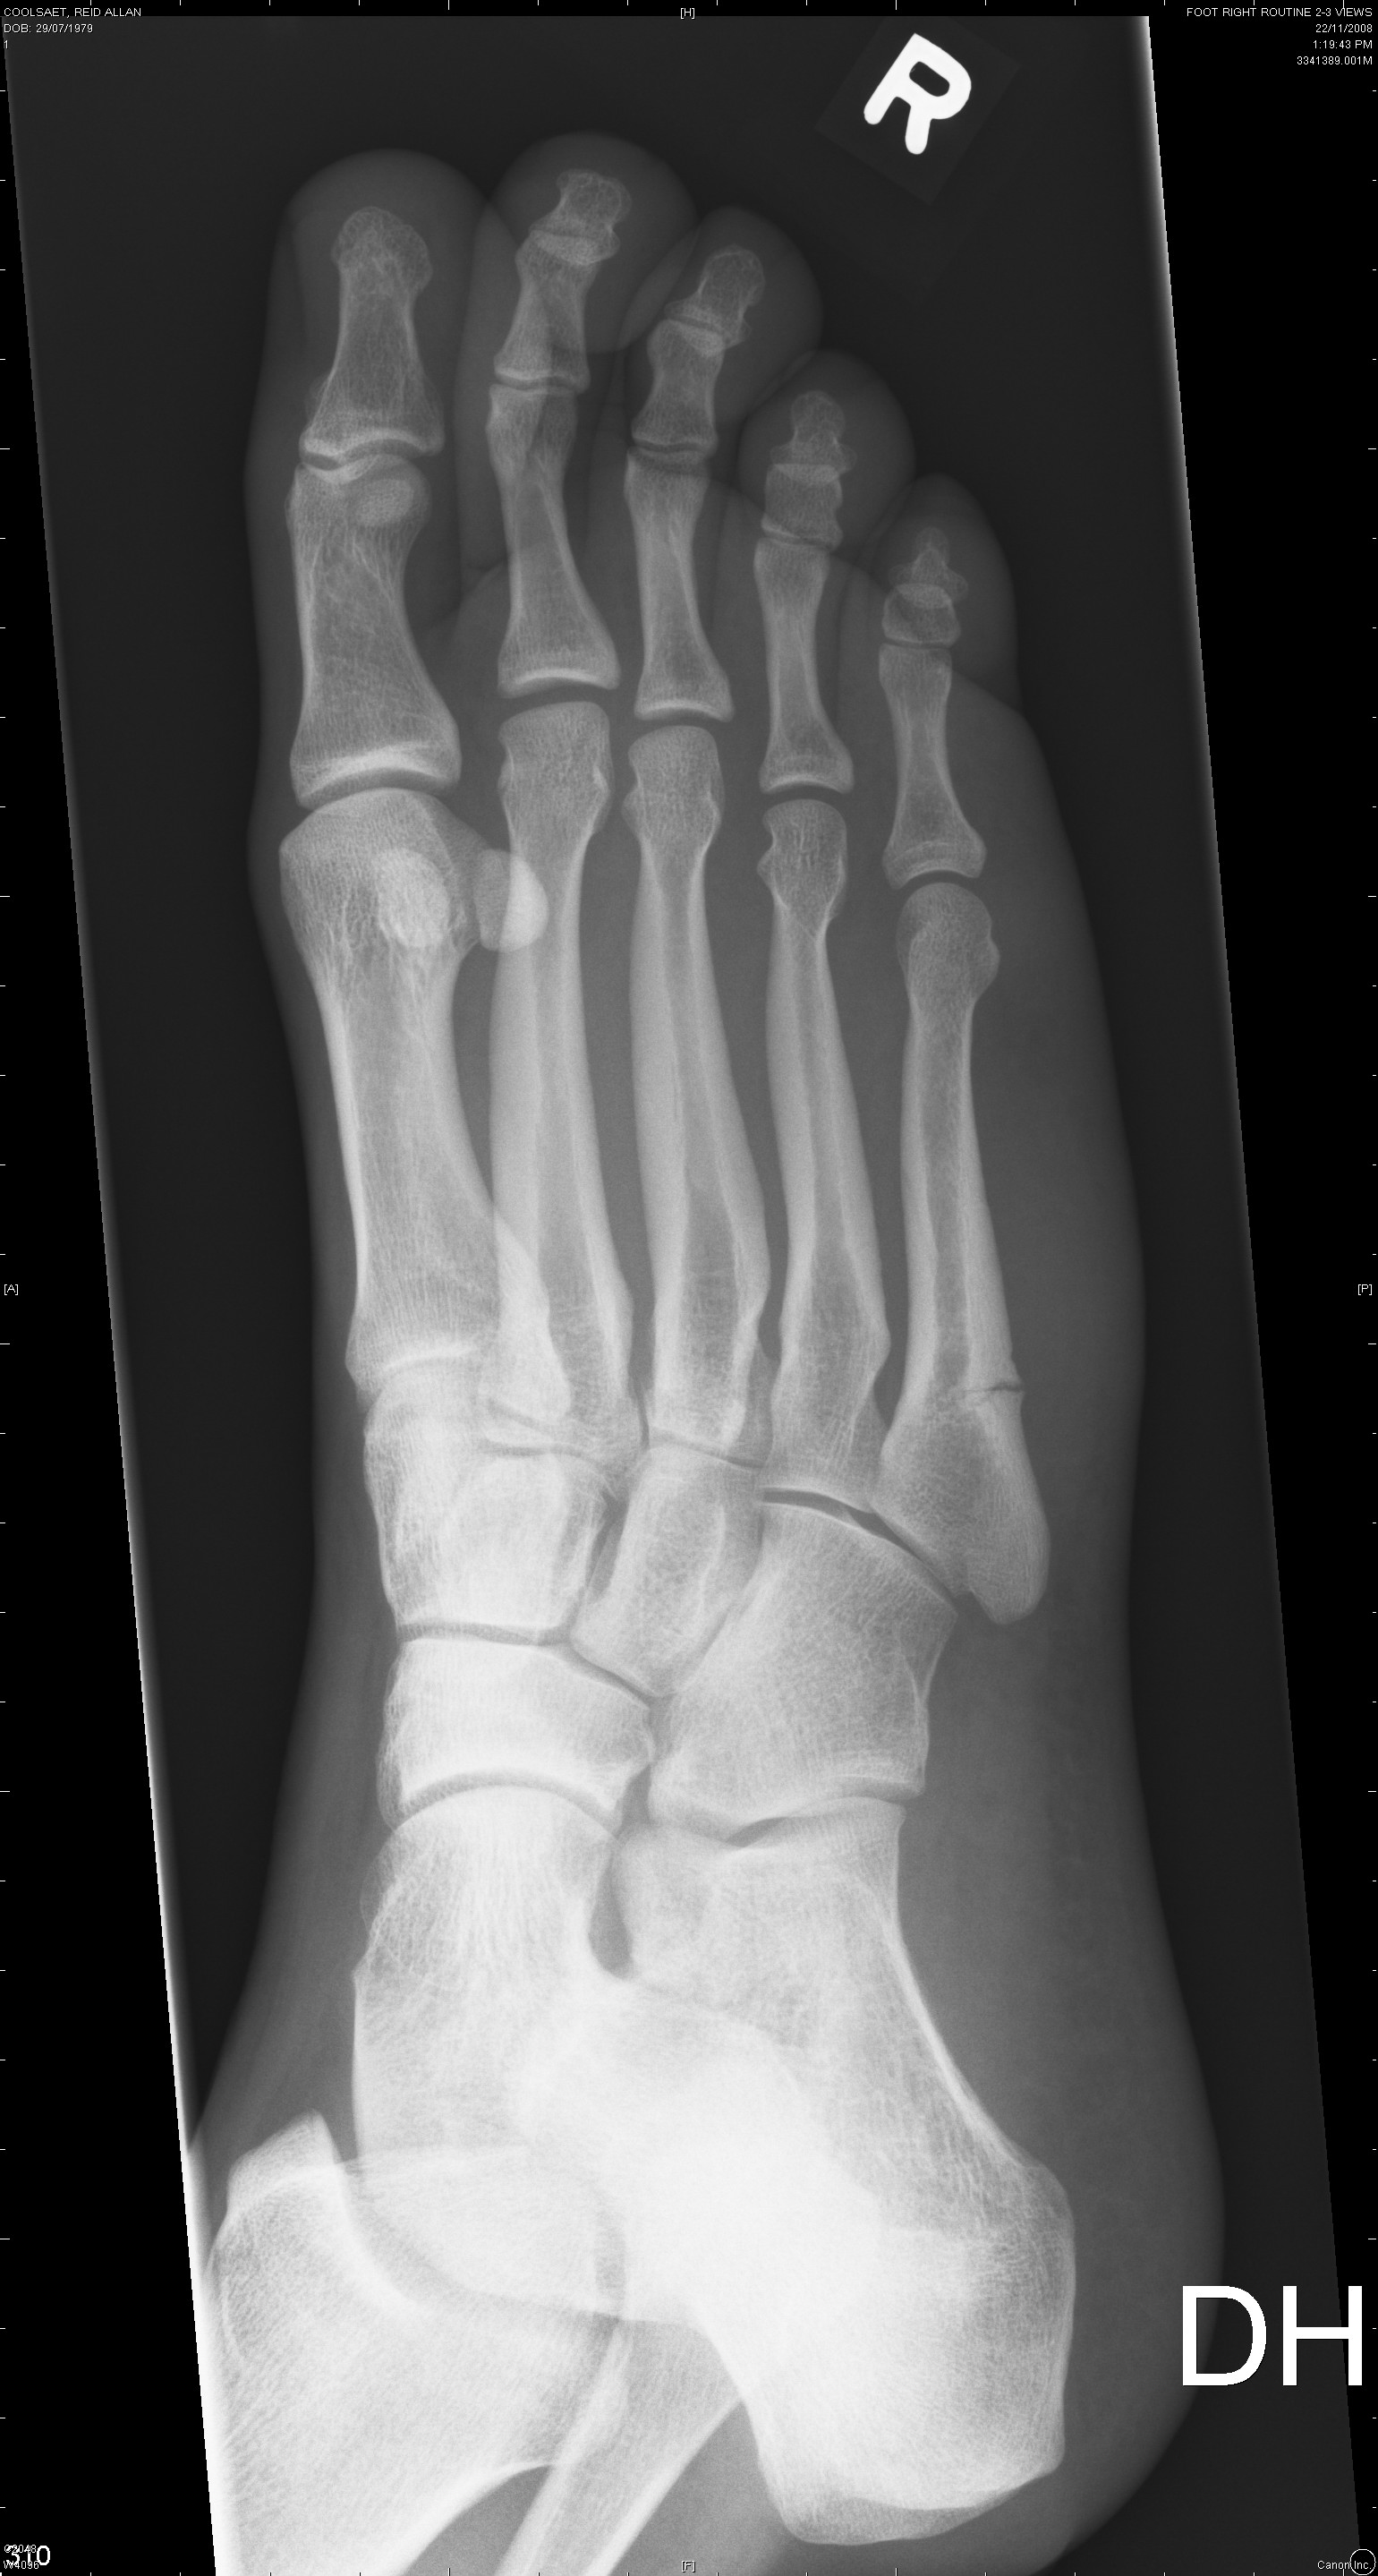

The first two are from November 6th and the last two are from November 22nd.

The fifth metatarsal (long bone on the far right) is broken.